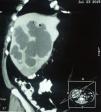

Caso clínicoMasculino de 57 años procedente de San Luis de la Paz, Guanajuato, de nivel socioeconómico bajo; con historia de cuadro de diarrea mucosanguinolenta acompañada de pujo y tenesmo por 2 semanas; agregándose 10 días de fiebre y dolor abdominal de moderado a intenso localizado en el cuadrante superior derecho, irradiado a hombro derecho. En la exploración: temperatura de 39° C; frecuencia cardiaca 100 lat/min; frecuencia respiratoria 20 resp/min y presión arterial de 95/60mmHg, peristalsis presente, dolor a la palpación en el hipocondrio derecho, hepatomegalia de 4cm por debajo de borde costal, puñopercusión positiva en el área hepática, sin signos de irritación peritoneal; se hospitaliza con el diagnóstico clínico de absceso hepático amebiano, se realiza ultrasonido abdominal (mostrando formaciones quísticas múltiples en hígado) confirmadas con tomografía contrastada de abdomen y gammagrafía (figs. 1 y 2); la citometría hemática con leucocitosis de 12,000 103/μl con neutrofilia del 78% y prueba serológica de aglutinación de látex positiva. Se prescribe metronidazol 750mg 3 veces/día por 10 días; es dado de alta a los 12 días de hospitalización, asintomático.